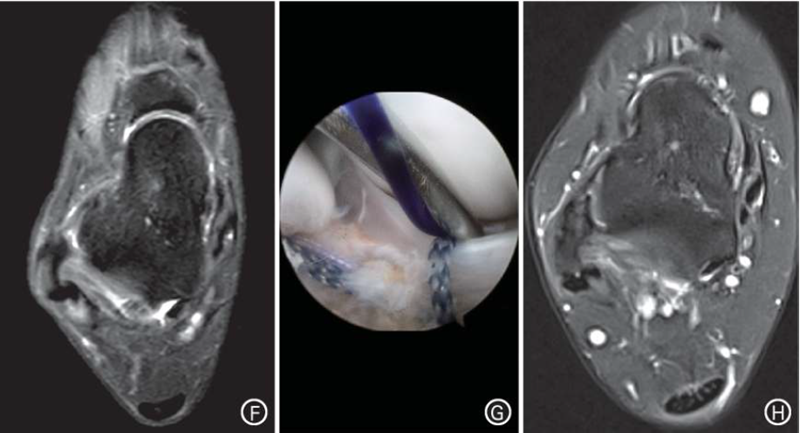

典型病例,患者男,19岁,右踝习惯性扭伤后疼痛不适1年余。入院诊断:(1)右踝关节ATFL损伤,慢性踝关节不;(2)全身多韧带松弛症(Beighton评分5分)。入院3d后行关节镜下改良Broström法ATFL修复术。

图1 A~E.患者体检显示Beighton评分为5分;F.术前MRI示右踝关节ATFL慢性损伤;G.术中将撕裂的ATFL残端通过锚钉缝线收拢至腓骨远端,然后打结拉紧;H.术后24个月MRI示右踝ATFL连续,未见明显松弛。注:ATFL为距腓前韧带